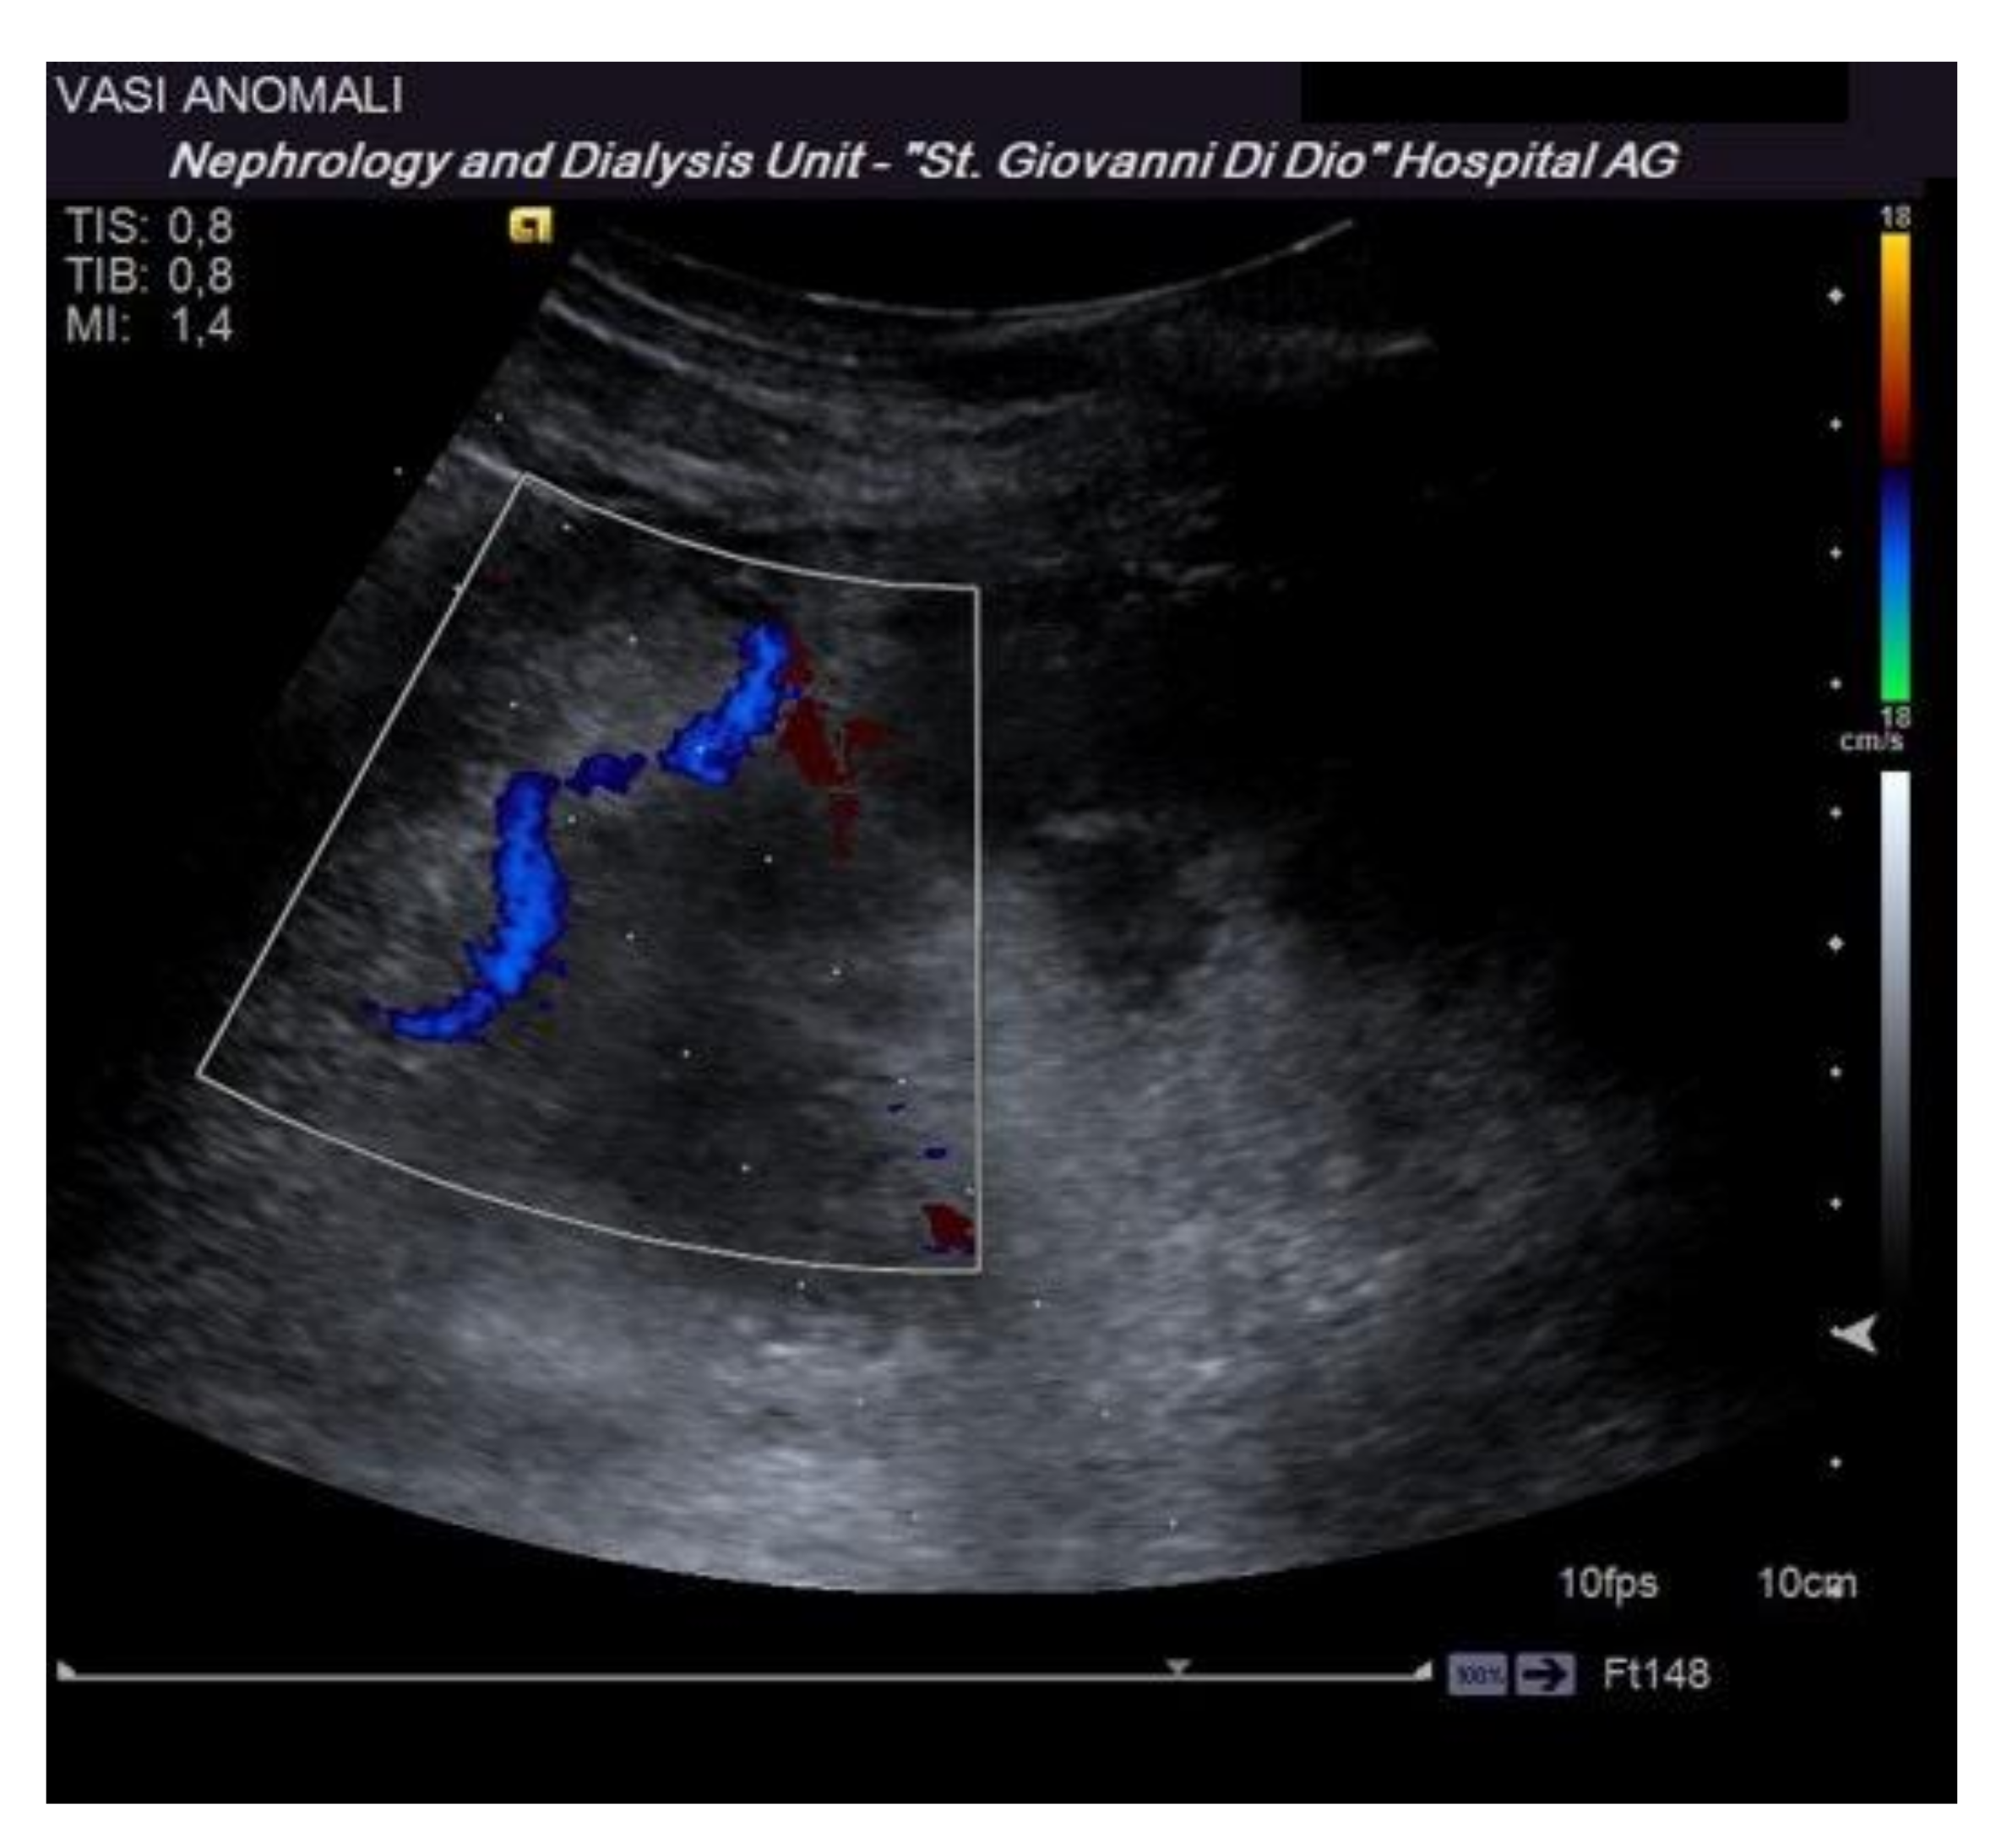

Before performing an ultrasound-guided PRB, it is advisable to perform a complete ultrasound examination of the kidneys in the same position as the procedure to evaluate the location of the kidney, its excursion during breathing, the cortical thickness, and the distance of the kidney from the skin surface. These data are useful to plan the procedure. Furthermore, this allows for the exclusion of anatomical variants (for example, horseshoe kidney), hydronephrosis, and cystic lesions, which may be contraindications for the procedure [16]. The examination must be completed with an ECD assessment to rule out the presence of vessels along the presumed path of the needle (Figure 3). Vascular abnormalities are reported in up to 10% of patients who undergo renal biopsy, and this may explain the reduction in complications observed when an ECD study preceded the procedure [15].

Figure 3.

The dotted lines show the expected trajectory of the needle when correctly fixed to the appropriate support. At the lower pole of the kidney, the site of the biopsy, there is an abnormal vascular formation that would have been crossed by the needle if it had not been recognized.